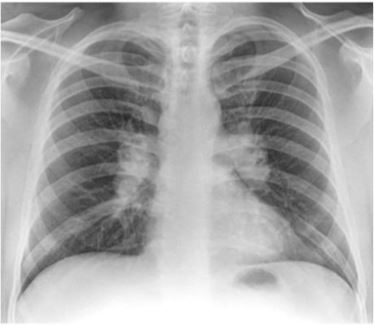

What does this x-ray indicate?

Bilateral hilar lymphadenopathy which could be lymphoma or sarcoid. If unilateral then it could be TB or metastatic spread.